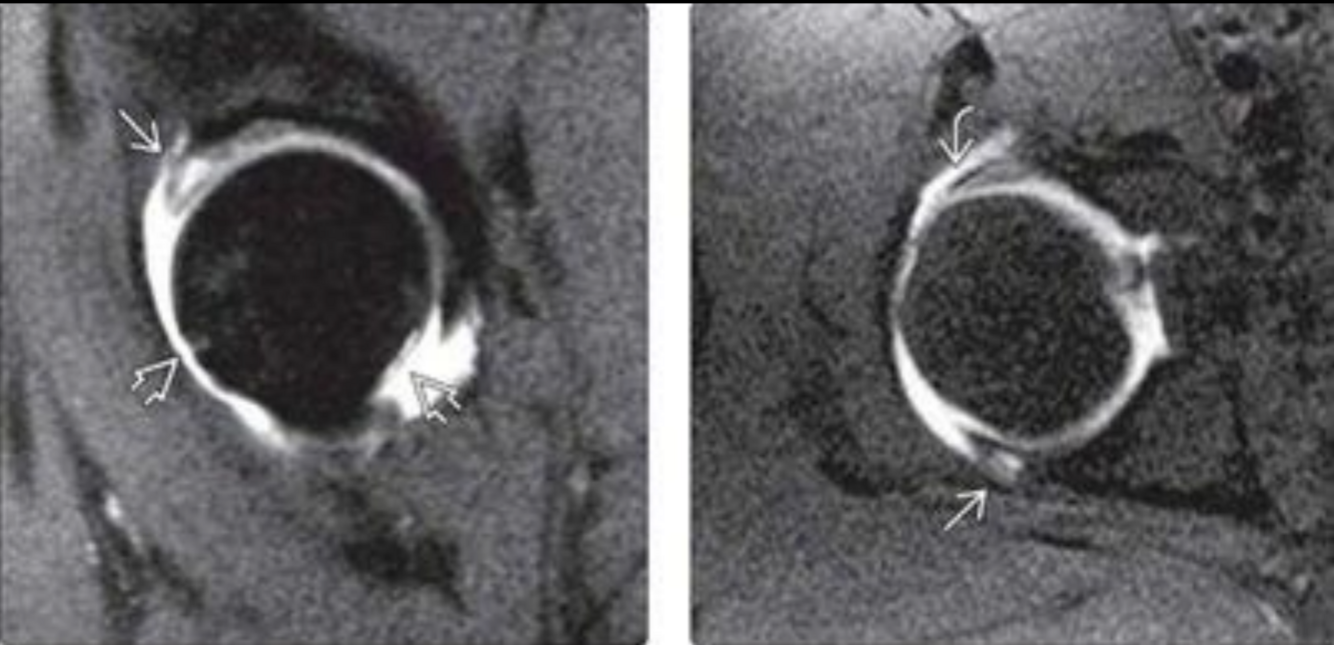

RM pinzamienro femoroacetabular

A

Edema óseo hiperintenso

Pinzamiento leve

Lesión del labrum

MIXED